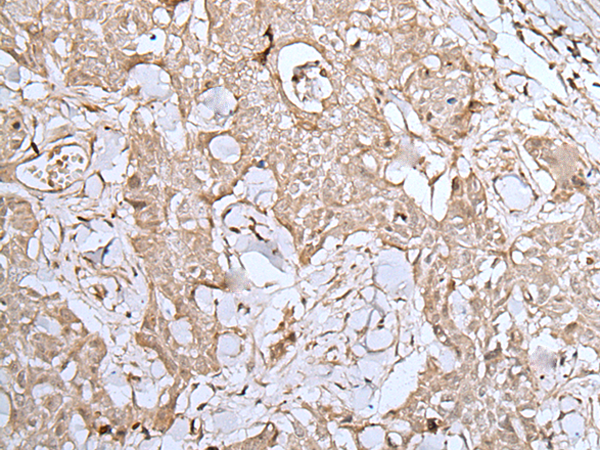

分类: 科研抗体货号: P12750别名: CBP1; CBP2; OI10; gp46; AsTP3; HSP47; PIG14; PPROM; RA-A47; SERPINH2应用: WB,IHC反应种属: Human, Mouse